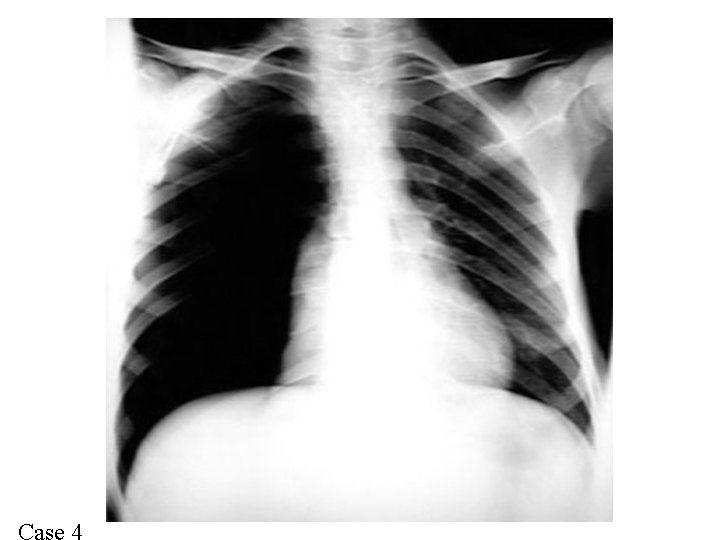

Case 1